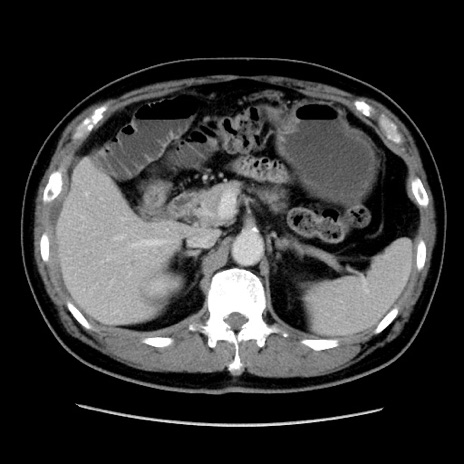

症例16(横断像)

【症例】 70歳代男性

【主訴】 腹痛、嘔吐

【現病歴】 約1ヶ月前より間欠的に腹痛と嘔吐あり、当院消化器内科を受診したところCTで多発する肝臓のLDAを指摘され、精査中であった。以降は消化器症状は安定していたが、2日前より嘔気と腹痛があり、同日より排便・排ガスが消失した。改善認めず、 本日、救急外来を受診した。

【既往歴】 大腸ポリープ切除後。

【身体所見】意識清明・会話良好、BT 36.3℃、BP 127/80mmHg、 P 80bpm、腹部:膨満あり、平坦・軟、上腹部正中および下腹部正中に圧痛あり、反跳痛なし、筋性防御なし。

【データ】WBC 7200、CRP 0.77